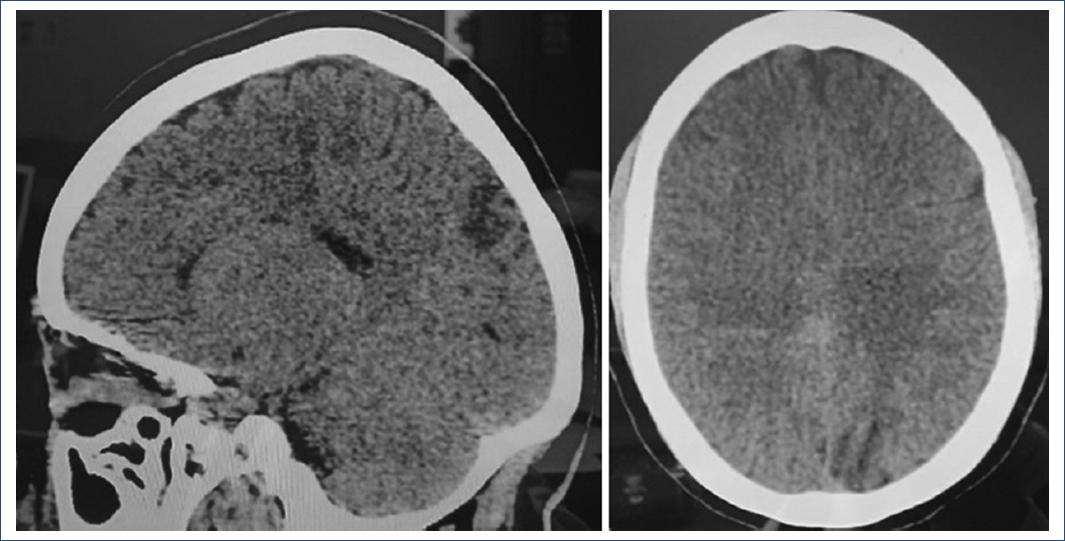

GCS 15 puntos: bilateral pupillary diameter 3 mm, brainstem reflexes and no cranial nerve alterations, unaltered motor sensitivity and response, preserved mental functions. Grade III osteotendinous reflexes. She was provided to neurocritical care on the recommendation of the neurology service, remained under deep sedation after cesarean section for 48 h, with ICP monitoring inferred by optic nerve sheaths diameter measurement ICP 12-14 mmHg, and subsequently emerged without data of delirium, without any manifestation of neurological deterioration. Tomography: Density changes compatible with thrombosis of the superior longitudinal sinus, without any other alteration at the intraparenchymal or ventricular level (Fig. 2).

Figure 2 Cranial tomography on axial projection, hypodensity corresponding to the affected area is observed. Source: Clinical record.